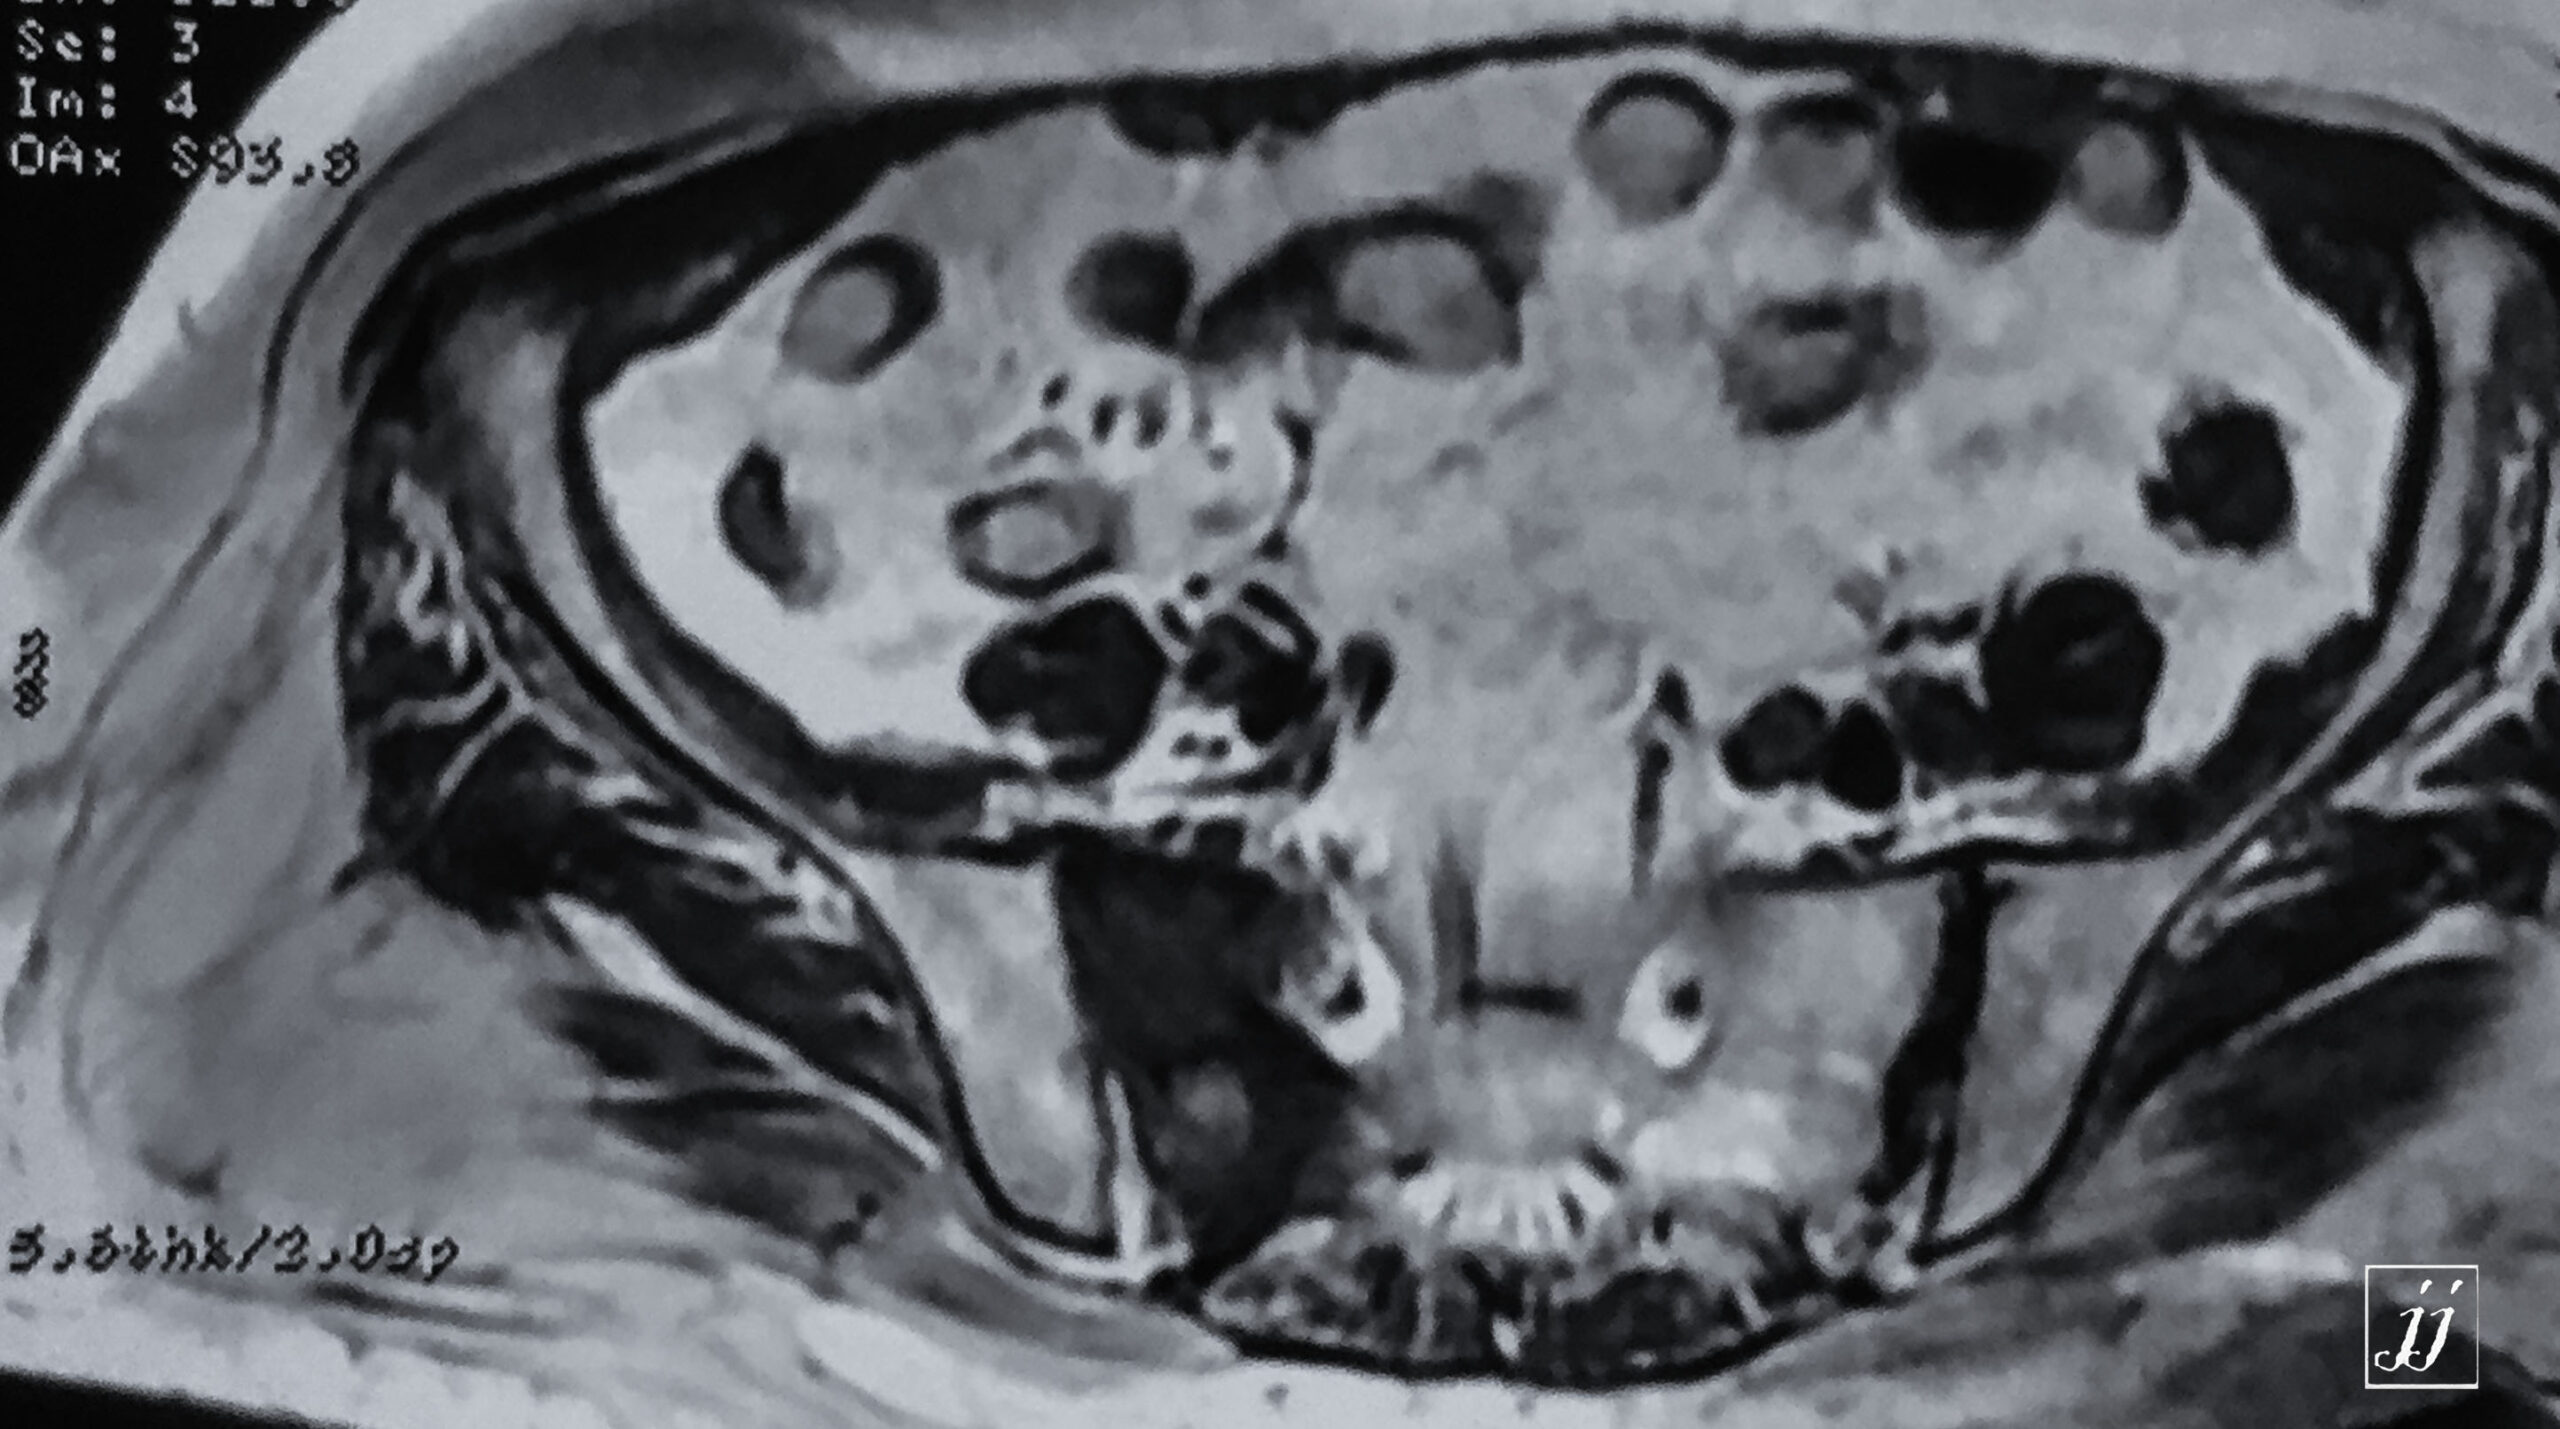

MSK- right pelvic floor muscular rupture and abnormal signal of right sacrum and pubic fracture (12)